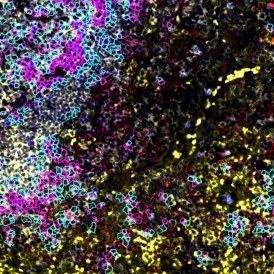

A Glimpse into StrataQuest 8: Spatial Analysis in Colorectal Cancer

The newest StrataQuest supports in-depth neighborhood analysis with exportable data for statistics. It includes manifold learning (t-SNE, UMAP, SONG), violin plots, 3D diagrams, and other tools that give full control of data.